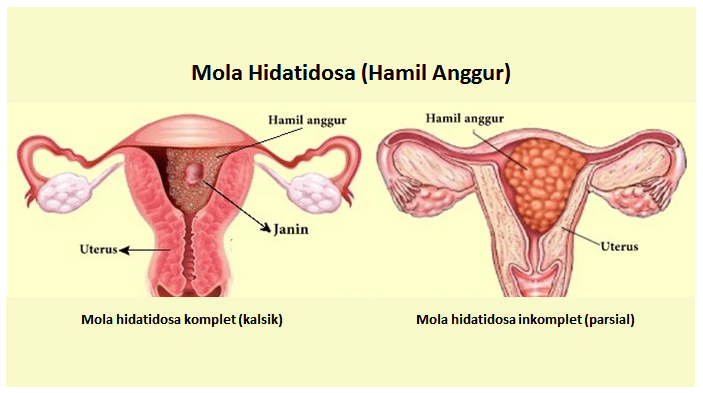

Kuliah Mahasiswa Kehamilan Anggur Mola Hidatidosa Youtube

Kuliah Mahasiswa Kehamilan Anggur Mola Hidatidosa Youtube

Mola Hidatidosa Hamil Anggur

Mola Hidatidosa Hamil Anggur

Mola Hidatidosa Hamil Anggur

Mola Hidatidosa Hamil Anggur

Mola Hidatidosa Hamil Anggur Stikes Surabaya

Mola Hidatidosa Hamil Anggur Stikes Surabaya